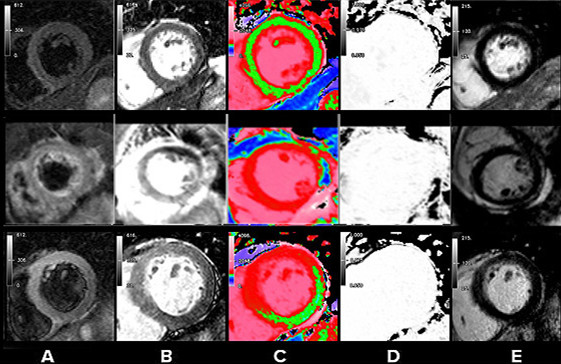

比较三名受试者在五种成像模式下的代表性短轴CMRI结果。

上排:正常普通志愿者。中间一排:TCM患者。

下排:患者心脏前壁局部水肿;前侧壁和前间隔显示高强度T2信号和T1(纵向弛豫时间)值较高。

A栏:T2 加权Dark-blood图像。B栏:T2 加权Bright -blood图像。C栏(绿色=正常心肌;红色=T1增加值):彩色ShMOLLI T1加权图像。D栏:ShMOLLI反转恢复序列的R2(弛豫速率)影像。E栏:钆剂延迟增强影像(LGE)。